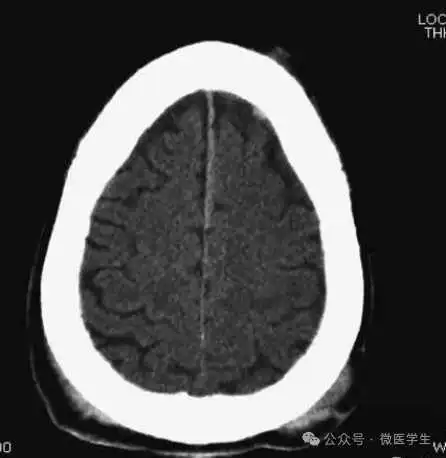

缺血性脑卒中

- 早期:脑水肿,灰白质分界模糊,脑沟消失;

- 中期:病变区域密度减低;

- 晚期:脑实质体积缩小。

A:陈旧性脑梗死,右枕叶体积缩小;

B:左枕叶急性脑梗死,灰白质分界模糊,脑沟消失;

另一患者:

C、D:亚急性期脑梗死,低密度,无明显占位效应。

▲

左侧大脑中动脉供血区脑梗死(亚急性期):

低密度,轻度水肿

缺血性脑卒中发作2-4天时,占位效应最明显。